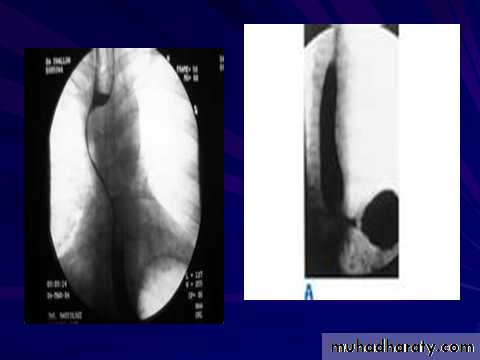

A chalasia Cardia

Narrowing :

1-the narrowing is Constant Short length (confined to cardia).

2-Regular and smooth.

3- No shouldering sign.

4-Tapering (Tip of pencil , cigar shape) Under left dome of diaphragm.

Achalasia continue

5. DILATATION (Sac like in proximal part )6-Undulating or spiky out line due to sluggish peristalsis.

7 Non- homogeneity of Barium due to food particles.

8-Air Barium level.

9- CXR shows widening of mediastinum.

10-Absence of fundal gas shadow.

7-Basal fibrosis in lungs due to repeated aspiration pneumonia .

LEFT: Dilated esophagus (arrows) appears as long, well-defined structure paralleling heart RIGHT: Dilated esophagus usually deviates to right. Narrowing (arrow) at hiatus.

LEFT: CT shows dilated esophagus (arrow) that led to esophagram.RIGHT: Esophagram shows narrowing (arrow) at level of hiatus.